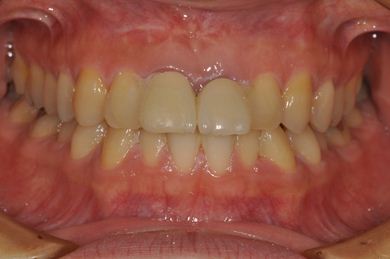

| 性別/年齢 | 女性 / 32歳 | ||||||||||||||||||||||||||||||||

| 主訴 | 前歯2本の差し歯がぐらついており、インプラントのセカンドオピニオンを希望。 | ||||||||||||||||||||||||||||||||

| 治療方針 | 上顎前歯、抜歯と同時にインプラントを埋入し、治療期間を短縮する。 | ||||||||||||||||||||||||||||||||

| 治療内容 | インプラント2本、メタルボンドセラミッククラウン2本 | ||||||||||||||||||||||||||||||||

| 総治療費 | 909,510円 | ||||||||||||||||||||||||||||||||

| 治療期間 | 1年0ヶ月 |